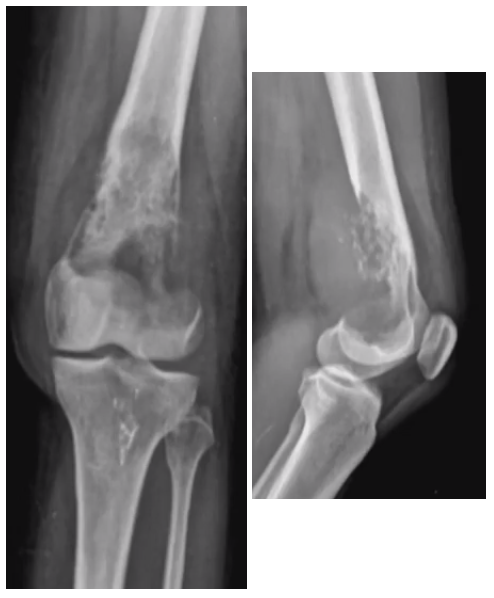

• Descreva a lesão:

A

• Osso esqueleticamente maduro

• Localizada no fêmur distal, predominantemente metafisária, acometendo medula e cortical

• Lesão única, de grande dimensão

• Lítica

• Sem padrões de conteúdo em específico

• Margens mal definidas

• Rompe a cortical medial, lateral e posterior

• Possui extensão para partes moles

• Sem reação periosteal visível